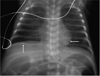

A premature infant with fetal myocardial and abdominal calcifications and factor V Leiden homozygosity

We present a premature male neonate with confirmed factor V Leiden deficiency diagnosed prenatally with cardiac and abdominal calcifications. Our patient's findings suggest that clinicians consider thromboembolic conditions when multiple fetal calcifications are visualized.